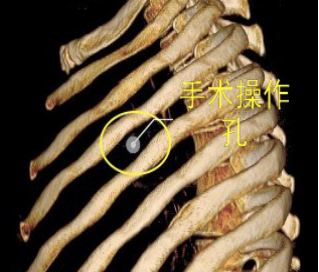

當前,絕大多數的肺大泡手術均可在電視胸腔鏡(VATS)下完成,2/3的患者術后癥狀明顯改善。與家長溝通后,鄧意平成功為小王開展單孔胸腔鏡下左側肺大泡切除術。

較兩孔、多孔胸腔鏡手術或傳統手術,單孔手術具有創傷更小、出血更少、術后疼痛更輕、瘢痕小、切口更加美觀、術后恢復快、住院時間短等優勢。但手術中所有器械(包括觀察鏡、吸引器、電凝鉤、切割閉合器、雙關節等各種操作器械)都要是從一個小“孔”進入,器械之間的互相干擾,同時器械與觀察鏡幾乎平行,視野非常狹窄,手術難度明顯,增加極其考驗醫生的技術。